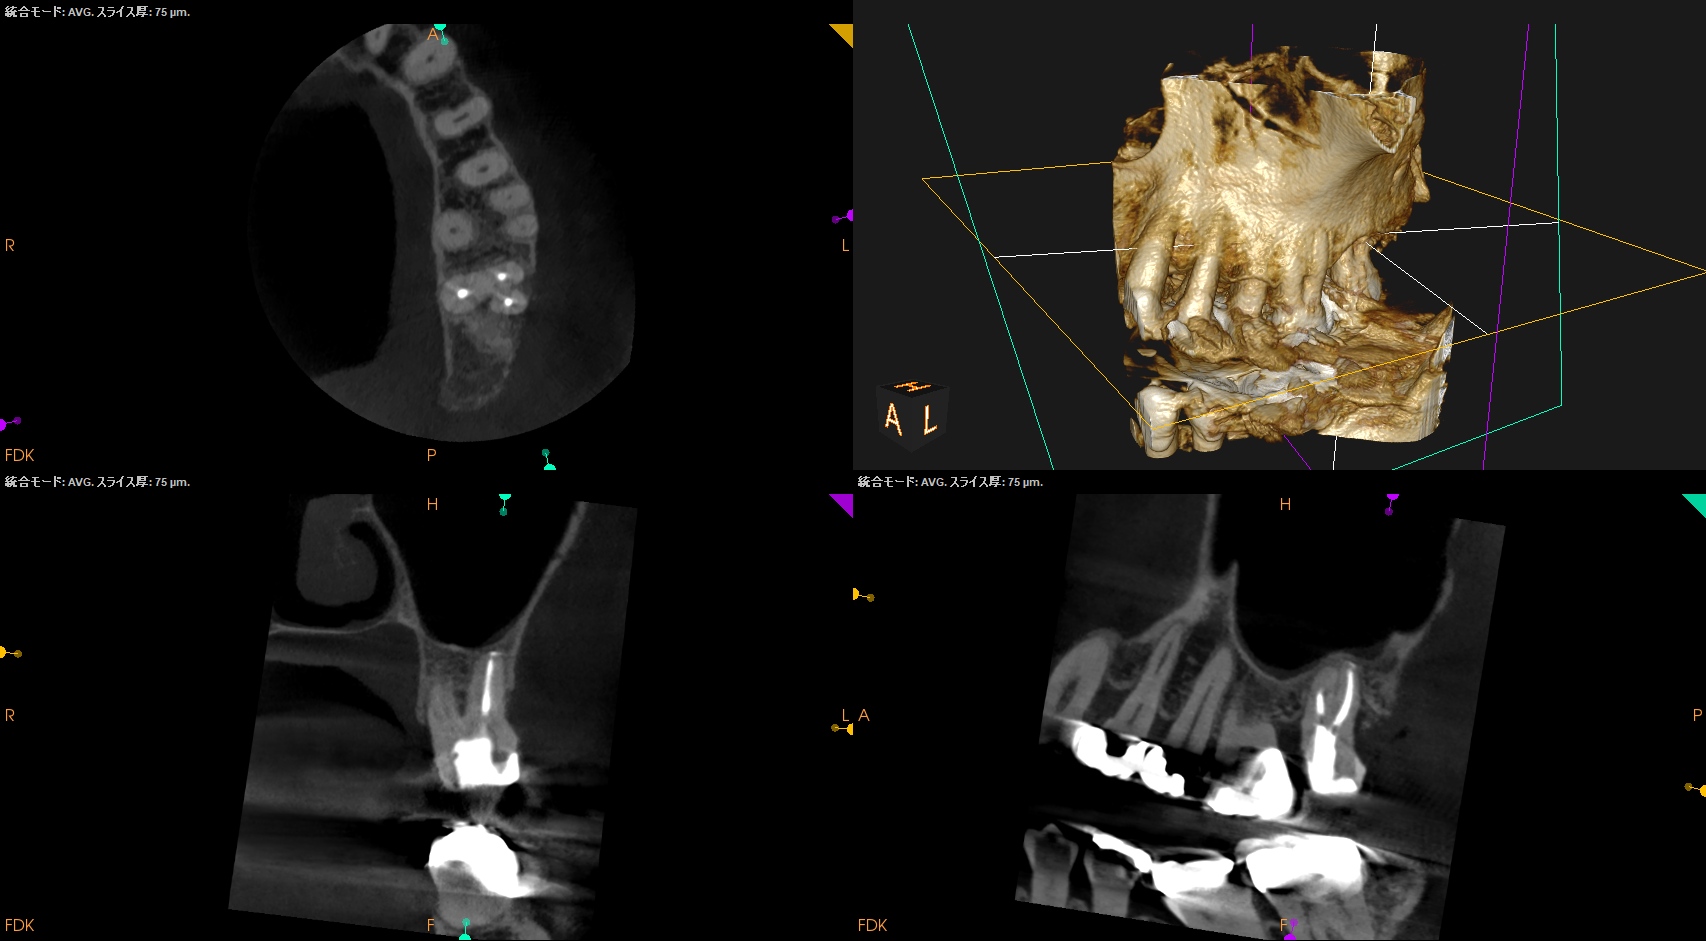

#15 RCT 1yr recall(2025.10.28)

MB

DB

P

初診時と比較した。

根尖病変、

術前の臨床症状、

術前の歯周ポケット

は完治した。

最終補綴もOKだ。